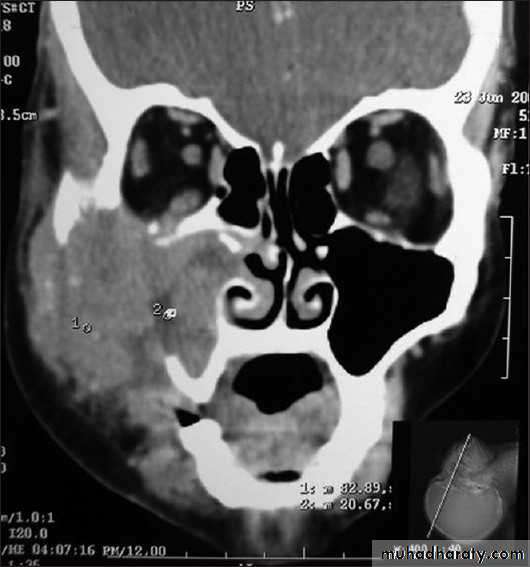

DIAGNOSIS:X-ray PNS.

CT Scan of PNS ( Coronal & Axial).

ETHMOID SINUS MALIGNANCY

Primary lesion is not common in ethmoid sinusOccur as an extension from maxillary sinus growth

C/F :

Nasal obstruction

Blood stained nasal discharge

Retro orbital pain

Lateral displacement of eye & diplopia